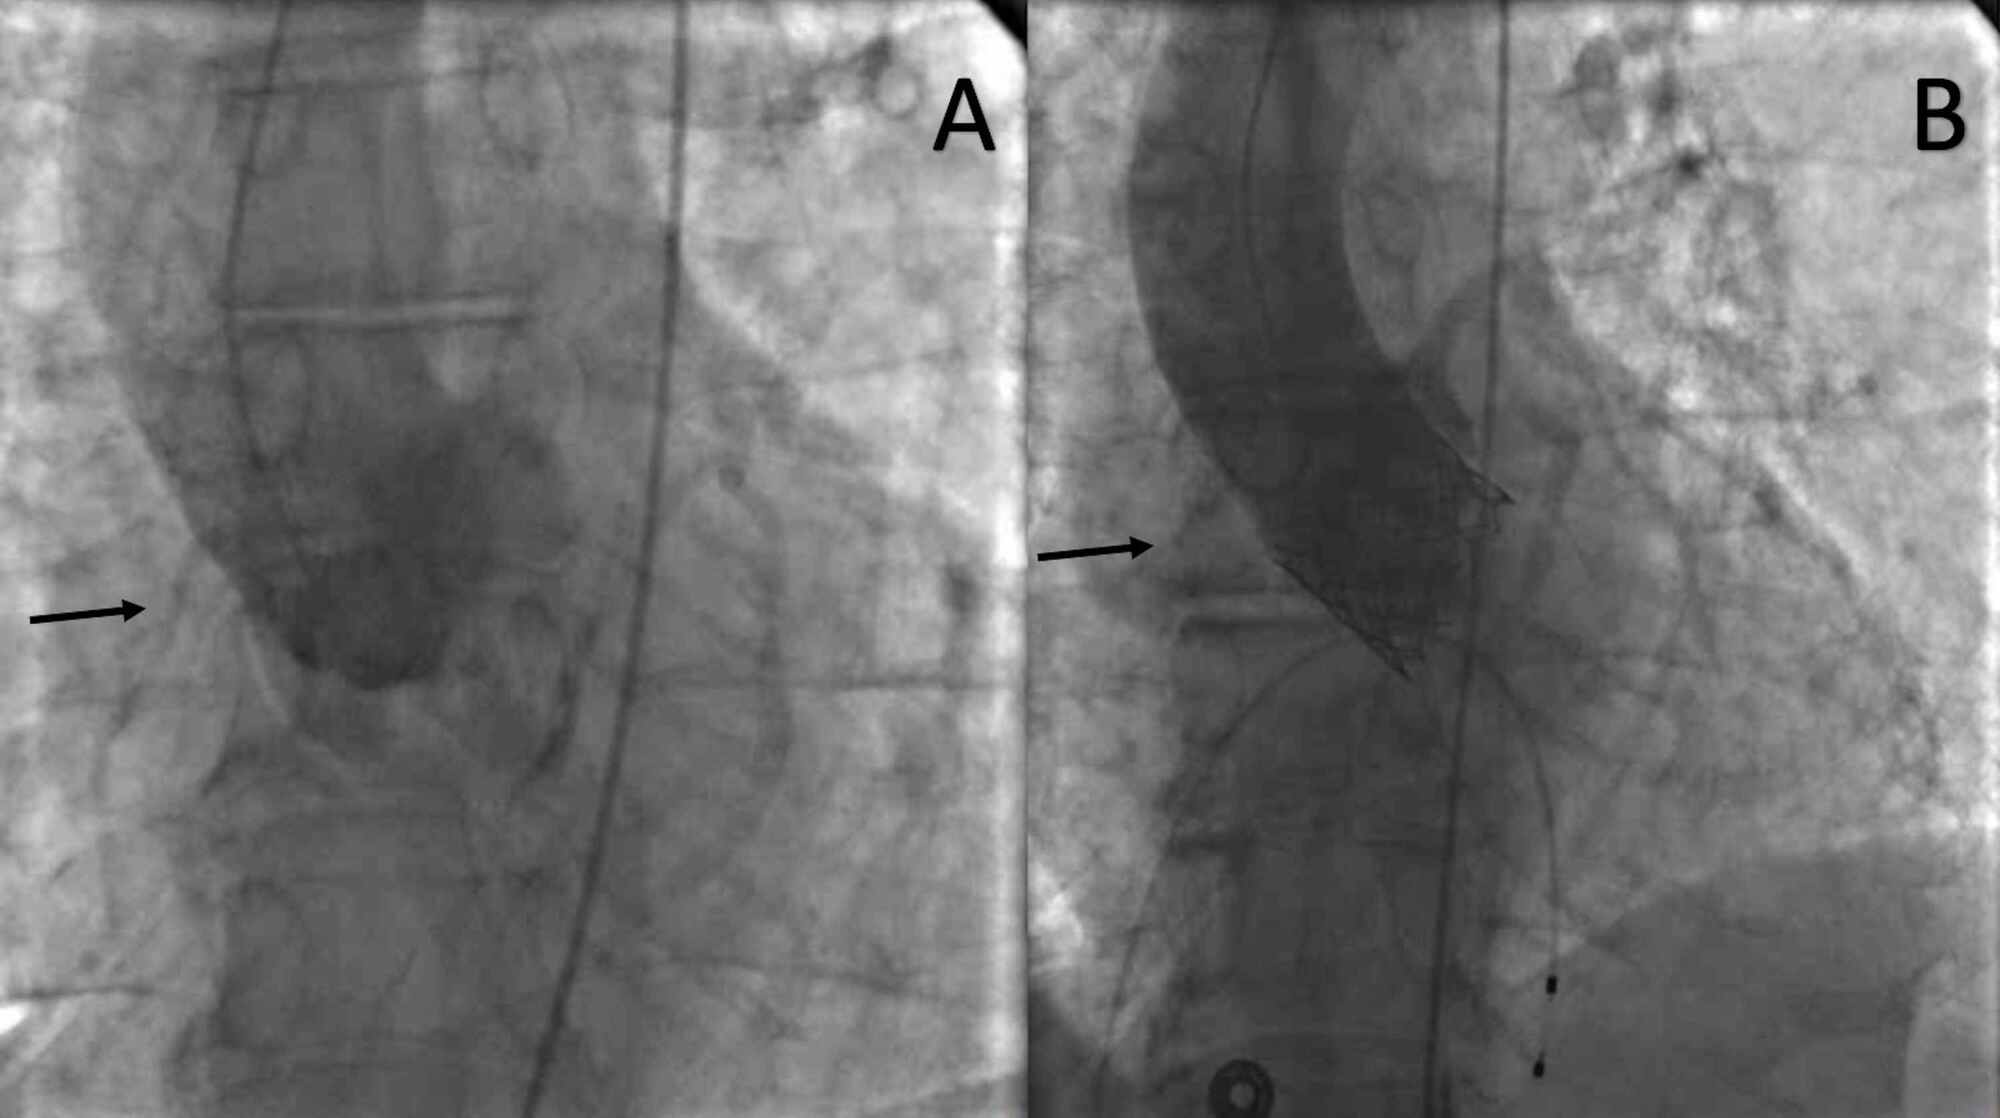

Coronary Angiography After Transcatheter Aortic Valve Replacement (TAVR Occlusion Valve Multidetector computed tomography (ct) is an important tool for assessing the risk of coronary occlusion in native valve tavr. The purpose of the valve is to restrict the exhaust side of. 8,13 although the optimal methodology for ct screening of the risk of coronary occlusion in the context of viv is still in evolution, the integration of ct screening has. Occlusion Valve.